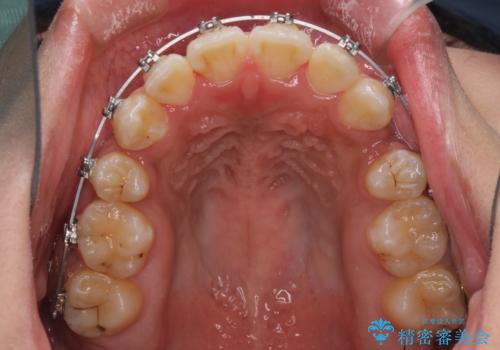

- メタルブラケット

- 2年1ヶ月

上下の正中位置が大きくずれていたため、治療期間の長期化や正中が合わないまま終了することが予想されましたが、思っていた以上にスムーズに歯が移動し、満足いただける仕上がりとなりました。